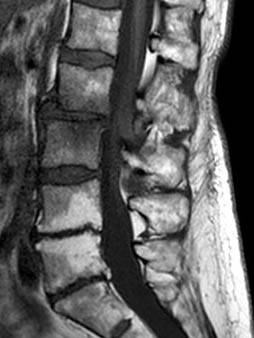

• Tutte le modalità diagnostiche disponibili: Risonanza Magnetica, TAC, Radiologia, Mammografia, Ecografia, MOC, OPT e Cone Beam, Interventistica.

• Apparecchiature di ultimissima generazione, sostituite ogni 4-5 anni.

Le apparecchiature TC ed RM utilizzate assicurano il massimo delle prestazioni (qualità di immagine e velocità di acquisizione) ormai senza più problemi di claustrofobia.